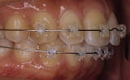

☆審美ワイヤー(光拡散型)の使用例と

ホワイトワイヤー(コーティング)での治療例

審美ホワイトワイヤー

光拡散ロジウムコートtypeワイヤー

ゴールドシリーズ審美ワイヤー

ホワイトコーティングtypeワイヤー